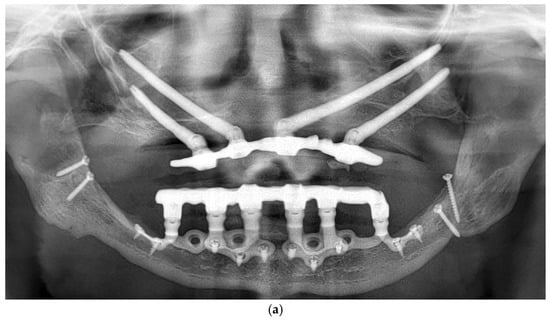

All patients were rehabilitated using custom-made subperiosteal implants, designed from the patients’ CBCT DICOM files to precisely match the anatomical features of each jaw. A fully digital workflow was used in all cases, including the RealGuide® software 5.4 for planning. The implants were designed as segmented frameworks, with two to four divisions per arch and 2–3 abutments per segment (Figure 2a–d).

Each subperiosteal implant was passively adapted to the bone and secured with titanium osteosynthesis screws to achieve primary stability (Figure 4).

Flaps were repositioned and sutured with resorbable Vicryl 4-0 sutures. Panoramic radiography and clinical pictures were obtained postoperatively (Figure 5a,b). Within 48 h, digital impressions were taken, and a provisional screwed PMMA prosthesis was delivered. In all patients, immediate loading was achieved without intraoperative complications. Postoperative care included Amoxicillin 1 g twice daily for 7 days, Ibuprofen 600 mg as needed, and Chlorhexidine 0.20% mouthwash twice daily for 14 days. Sutures were removed after 14 days.

Figure 5.

(a) A panoramic radiograph of the patient after subperiosteal implants placement. (b) Intraoral picture of the mandible following subperiosteal implant placement.